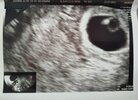

Ja po wczorajszej wizycie i braku czegokolwiek na usg się załamałam ale już mam wynik dzisiejszej bety, przedwczoraj wynosiła ona 98,77 a dziś już 226,30

Przyrost o 130% także trochę już się uspokoiłam,mam nadzieje ze w końcu uda się na usg coś zobaczyć następnym razem